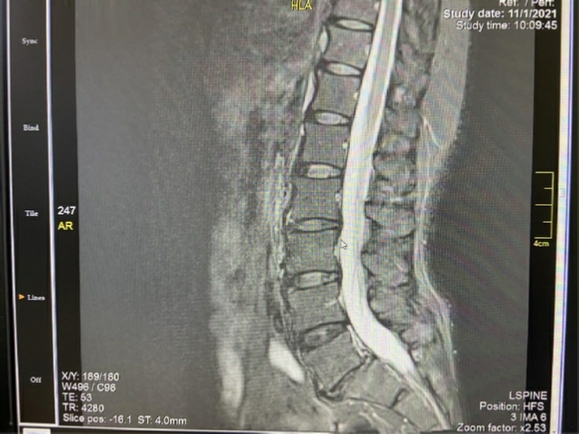

Στις δύο ανωτέρω εικόνες είναι εμφανής η έντονη εκφύλιση του μεσοσπονδυλίου δίσκου Ο5-

Αυτή η περίπτωση είναι ιδανική για διενέργεια πρόσθιας διασωματικής σπονδυλοδεσίας, η οποία και διενεργήθηκε με τη χρήση ευρέως κλωβού και μίξη αυτομοσχεύματος από το λαγόνιο (μέσω της ίδιας τομής) και DBM. Σταθεροποίηση με τρεις βίδες με πολύ καλή συγκράτηση και συμπίεση του κλωβού. Ακολουθούν οι μετεγχειρητικές ακτινογραφίες.